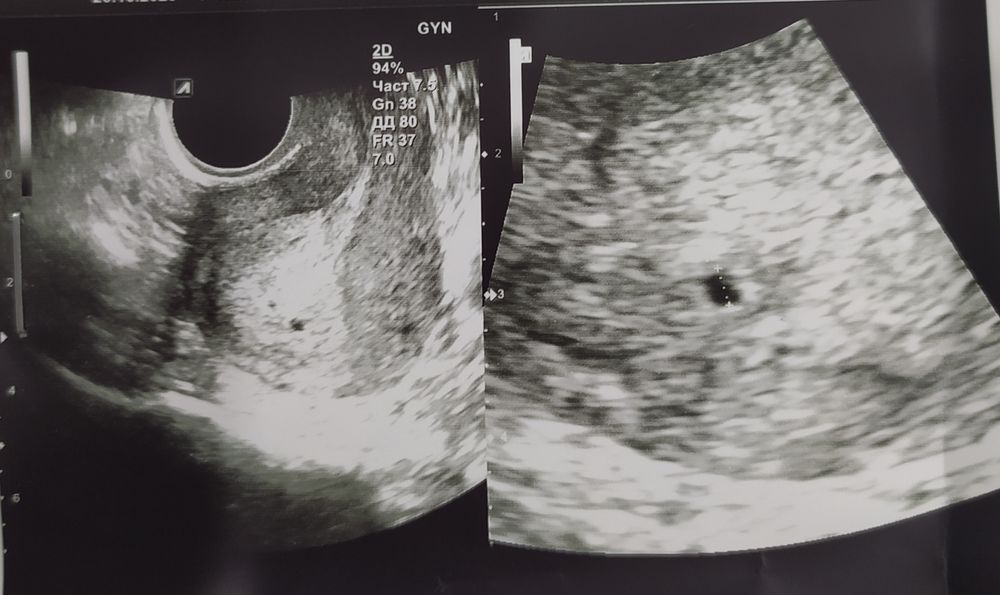

Это что две точки, Узист сказала одна плода мне кажется это двойным

Изображение

Одна плода.